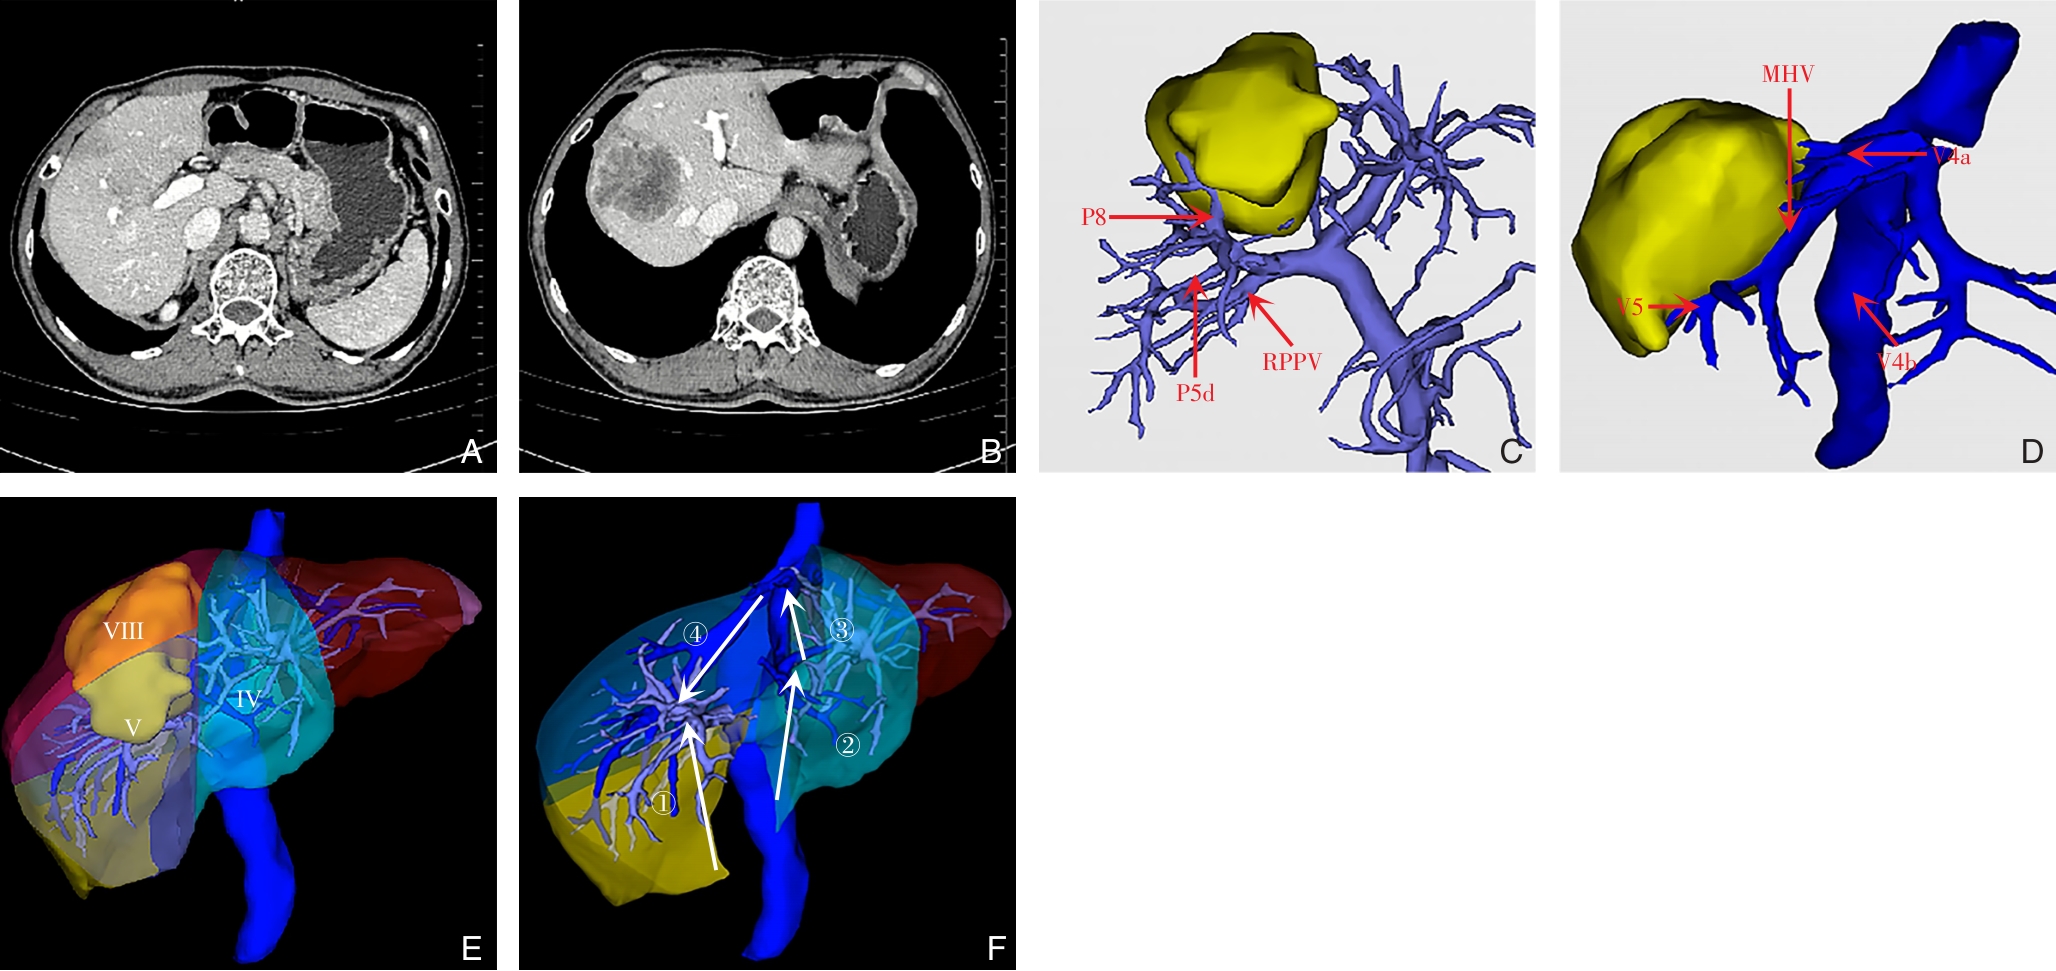

• Applied anatomy of segmental Glissonian pedicles at the hepatic hilum guided by the Laennec's membrane concept and its value in laparoscopic surgery

2026, 35(1):77-87. DOI: 10.7659/j.issn.1005-6947.250378

Abstract (111) HTML (79) PDF 2.06 M (165) Comment (0) Favorites

Abstract:Background and Aims Precise identification and control of segmental Glissonian pedicles are fundamental to laparoscopic anatomical liver segmentectomy. However, marked anatomical variations, particularly in the right hemiliver, pose significant technical challenges. Based on the anatomical concept of the hepatic Laennec's membrane, this study aimed to systematically investigate the applied anatomy of Glissonian pedicles at the hepatic hilum and to establish practical anatomical landmarks for laparoscopic anatomical liver resection.Methods Six intact adult human liver specimens without macroscopic lesions were dissected under the guidance of the Laennec's membrane concept. The segmental Glissonian pedicles at the first porta hepatis were meticulously isolated, and the intervening liver parenchyma was removed. The origin, branching patterns, and spatial courses of Glissonian pedicles in each hepatic segment were analyzed. For the right hemiliver, a localization system consisting of four anatomical landmarks, two reference lines, and four characteristic angles was proposed and quantitatively evaluated using specimen measurements combined with CT imaging and three-dimensional liver reconstruction.Results The intrahepatic Glissonian system demonstrated both consistent patterns and pronounced individual variations. In the left hemiliver, the Glissonian pedicles of segments Ⅱ and Ⅲ usually arose independently, while segment Ⅳ commonly presented a bifurcated pattern with occasional multiple branches. In contrast, the right hemiliver showed substantial variability: segment V pedicles were frequently multibranched and often received contributions from segment Ⅵ; segment Ⅵ served as a pivotal pedicle with multiple branches contributing to segments V and Ⅶ; segment Ⅶ most commonly originated from the root of the right posterior pedicle, although in some cases it was formed by distal extensions of segment Ⅵ; segment Ⅷ pedicles were relatively constant in morphology, typically consisting of one or two branches. The proposed anatomical landmarks and quantitative parameters enabled clearer spatial localization of segmental Glissonian pedicles in the right liver.Conclusion Systematic dissection of segmental Glissonian pedicles guided by the Laennec's membrane concept, together with a quantitative anatomical landmark system, enhances the understanding of their spatial anatomy and variations. This approach provides practical and reliable anatomical guidance for precise and safe laparoscopic anatomical liver segmentectomy.